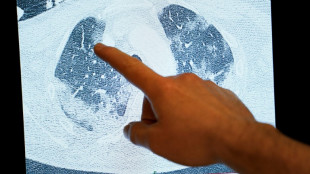

Vacuna contra cáncer de piel podría estar disponible en 2025, dice director ejecutivo de Moderna

El director general de Moderna, Stéphane Bancel, dijo a la AFP que la vacuna experimental contra el melanoma que elaboró su compañía podría estar disponible en tan solo dos años, lo que supondría un paso histórico contra la forma más grave de cáncer de piel.